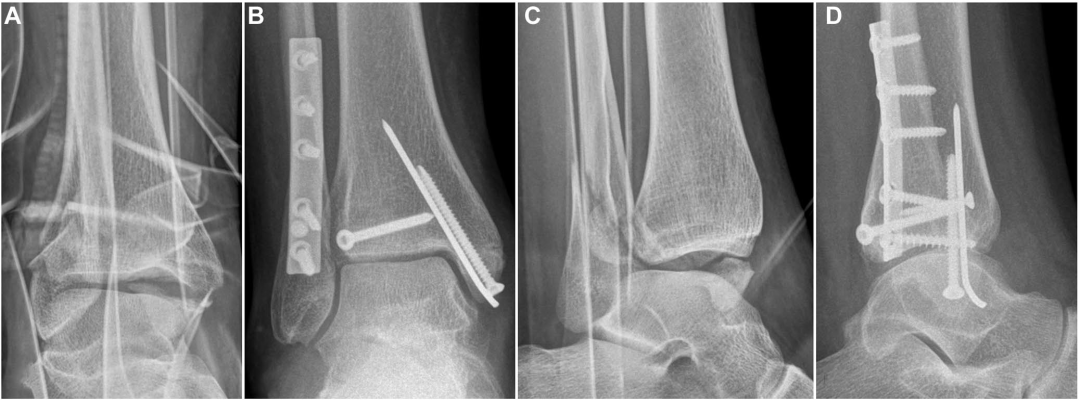

标准治疗:早期开放复位内固定(ORIF)

手术顺序:

复位腓骨 → 2. 固定后踝 → 3. 固定内踝/韧带 → 4. 检查下胫腓稳定性

手术入路选择:(后外侧入路可以很好的显露腓骨于胫骨后侧的卡压,使用撬拨技术先复位腓骨)